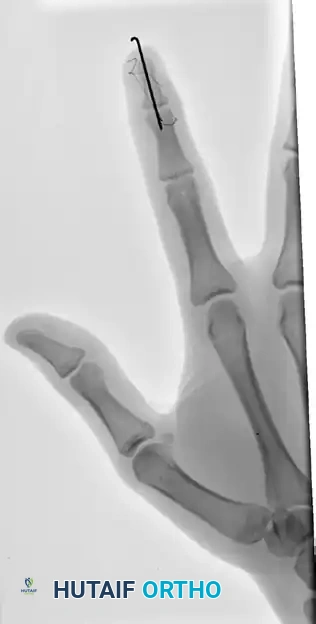

FIGURE 67-66 A: Type 4 bony mallet finger in a high-demand athlete, demonstrating a large dorsal fragment and volar subluxation of the distal phalanx.

FIGURE 67-66 B: Radiographic results of the pull-out wire and transarticular pin fixation of the distal interphalangeal joint, demonstrating anatomic restoration of the articular surface. Images taken just before pin removal at 4 weeks.